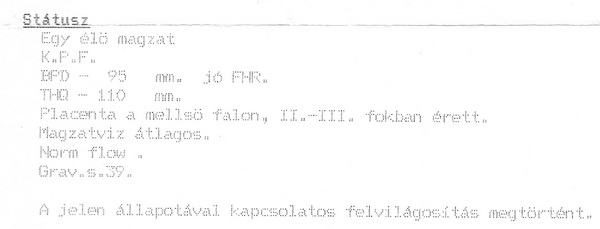

Én is voltam ma UH-n, legközelebb majd a kórházba megyek keringés vizsgálatra.

Most belehúzott a leányzó, két hét alatt sokat növesztett a kobakján. Így is kisebb másfél-2 héttel, de a lényeg, hogy növekszik, behozott a lemaradásból. Így E. doki is megnyugodott